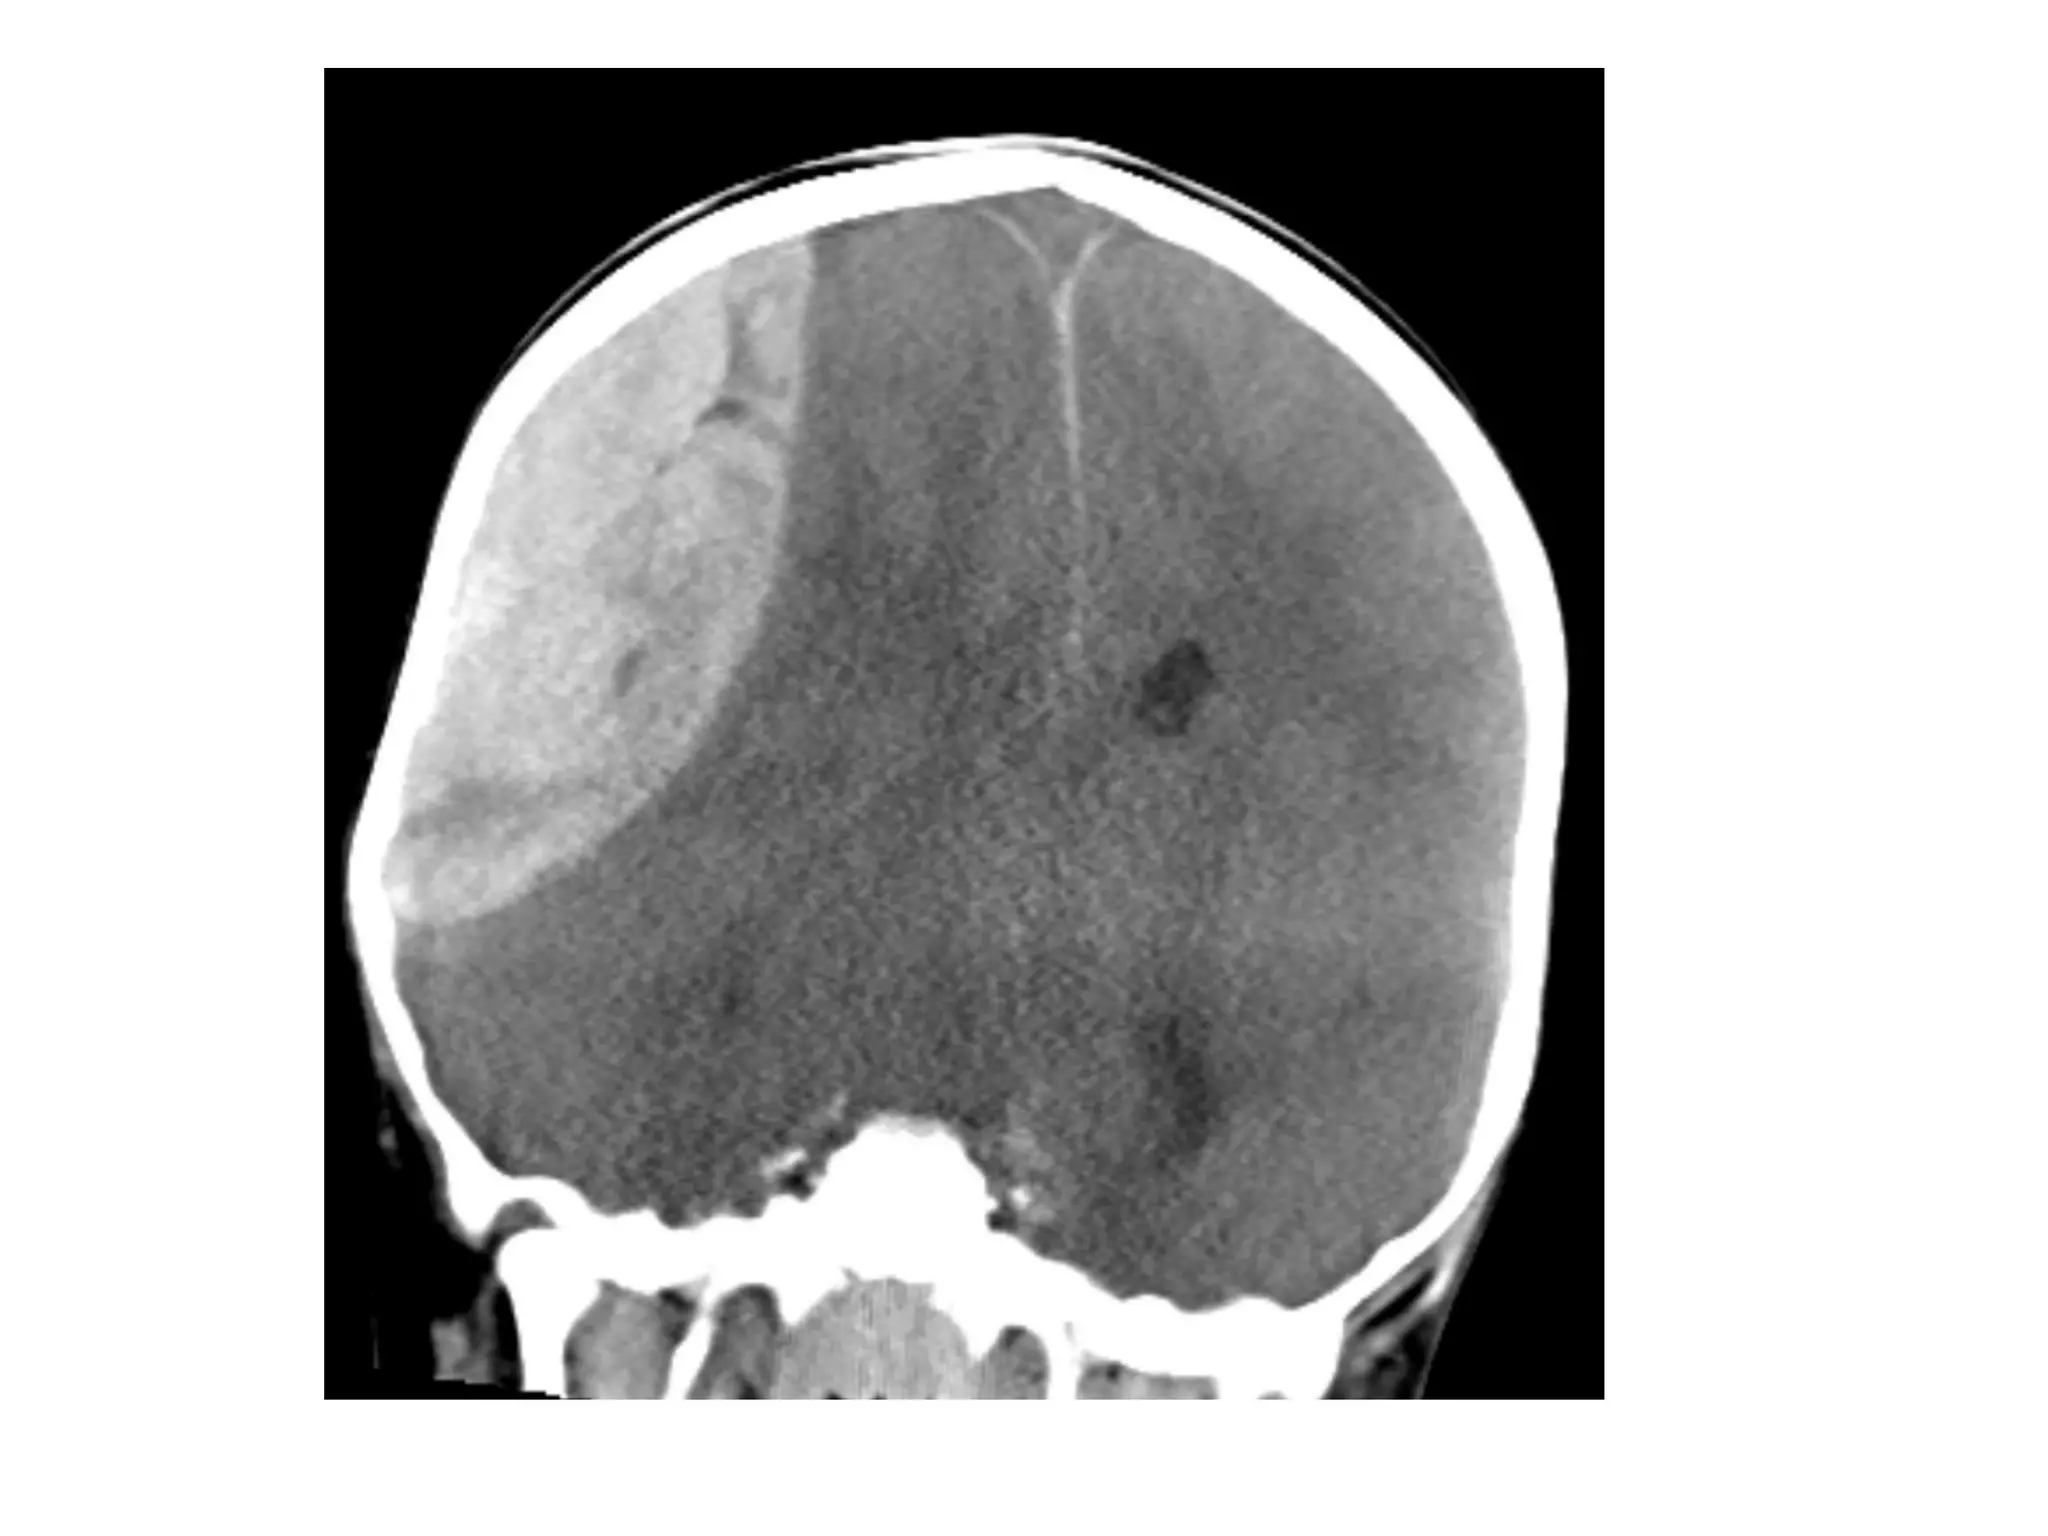

b) Generalized Mass Effect :

-Ventricular or basal cistern effacement +/-

midline shift (subfalcine herniation) or other

herniation syndromes : uncal , transtentorial

Midline Shift